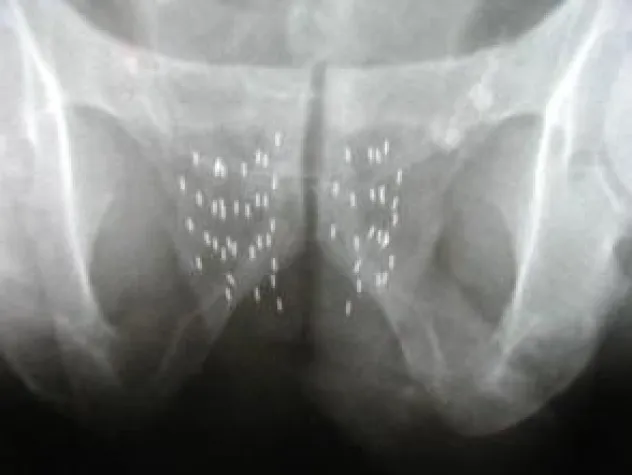

Röntgenaufnahme zeigt die präzise Verteilung der Seeds in der Prostata

Die Brachytherapie hat einen wesentlichen Vorteil gegenüber der Operation: “Durch eine exakte Verteilung der Strahlendosis können wir den Tumor bestrahlen, ohne umliegende Strukturen wie Harnröhre oder Schließmuskel zu beschädigen“, erklärt Dr. Gregor Spira, Strahlentherapeut im WPZ. So zeigen mehrere Studien, darunter eine US-amerikanische Studie vom August dieses Jahres, dass eine erek-tile Dysfunktion nach der Radikal-OP bei 70 Prozent und nach der Seed-Implantation bei 14 Prozent auftritt4. Auch die Harninkontinenz, die nach der radi-kalen Entfernung der Prostata bei bis zu 50 Prozent liegt, ist mit 0,3 bis 3 Prozent nach Seed-Implantation verschwindend gering und tritt eigentlich nur nach voran-gegangener Prostataausschälung (TURP) auf.